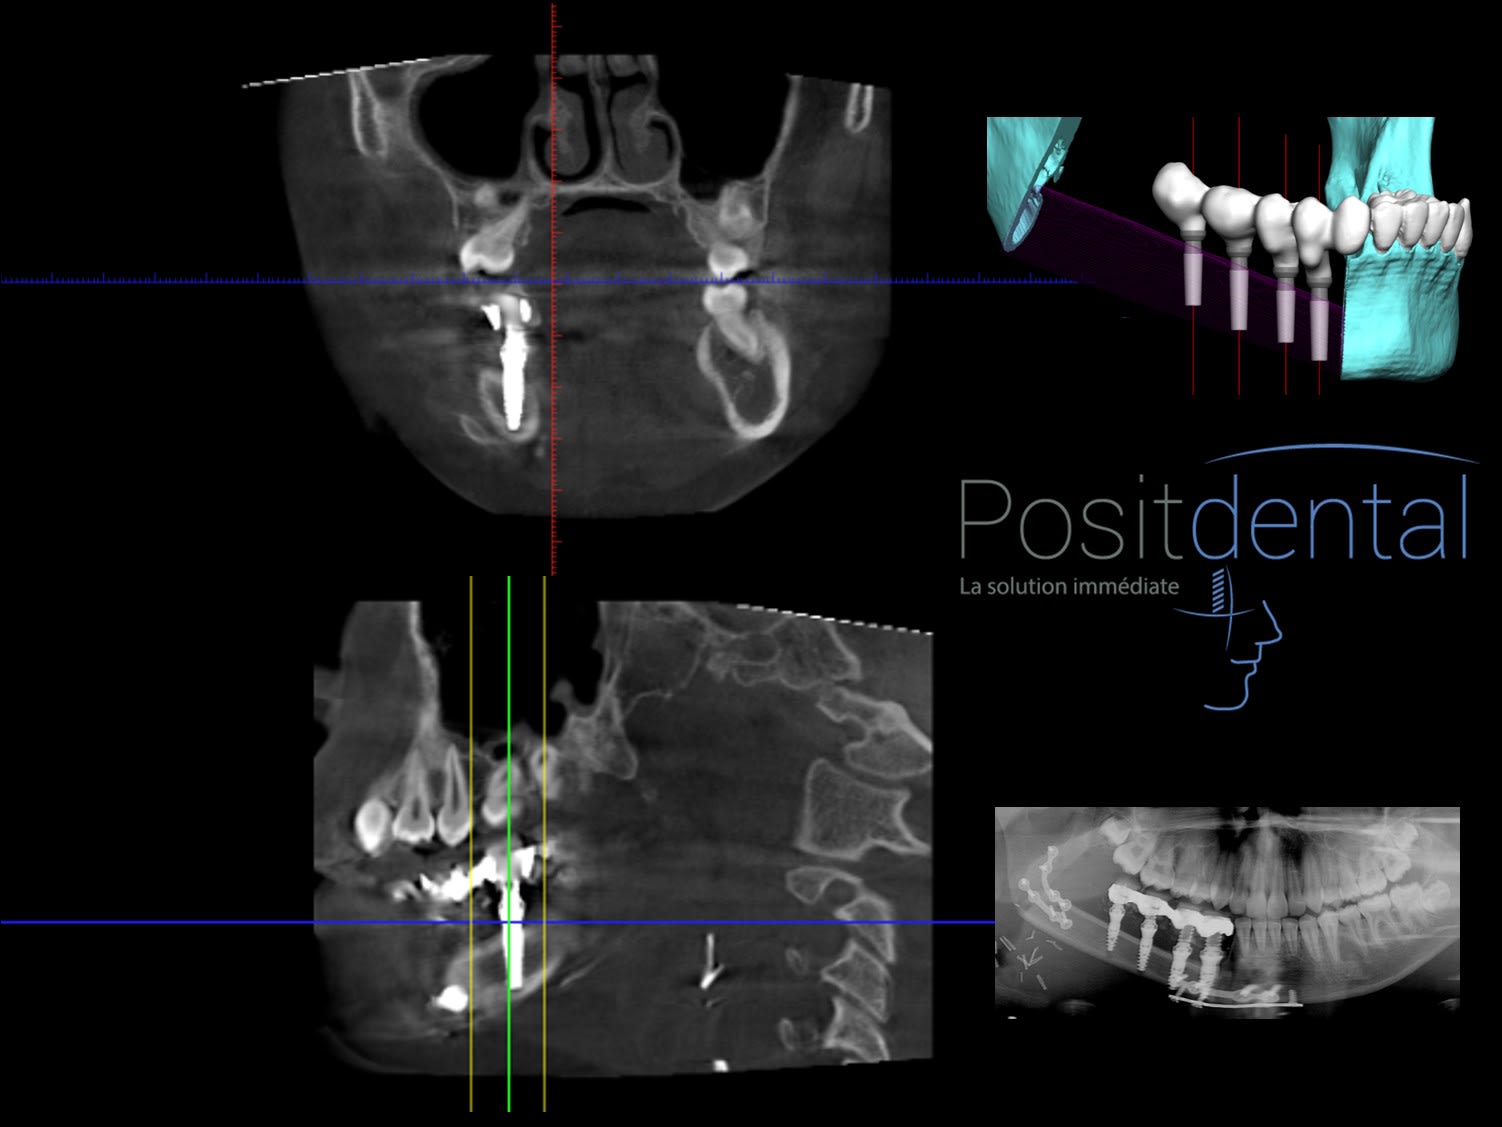

Comment tu expliques la disparition d'éléments anatomique sur cette pano ?

Bien sur que sur cette pano le col des 2 implants distaux son bien supra osseux et les mésiaux et surtout le second infra-osseux mais indéniablement les spires apicales semble avoir perforés la corticale, alors !!!

Stop bouboule, reprend le truc à la base. T'es partie sur affirmation d'hokusai :

1 / Les spires c'est à l'apex > voila pourquoi la photo de la greffe montrant le coté où ces spires pourraient apparaitre

2/ Les spires des implants en mésial qui semblent perforer la corticale sur la pano ne le font pas en clinique et tu voudrais que je ne me pose pas de question ?

Parce que :

j'était présent lors de la pose

j'ai vu le moteur bloquer à 50nw

que l'enfouissement à été vérifié par le fenêtre du guide

que cet implant de 10 à été foré avec le foré de 11.5

que pour un cas comme celui là perdre l'ancrage par des spires qui arrachent la matière en butant sur la corticale compromettraient toute l'intervention

qu'hokusai a extrait un détail pour transformer la réalité et que tu l'as suivi sans prendre le temps d'analyser ou poser des questions avant de tirer des conclusions

J'espère que tu apprécies la perception de l'éclaircissement

L'apex des implants sont dans la corticale.